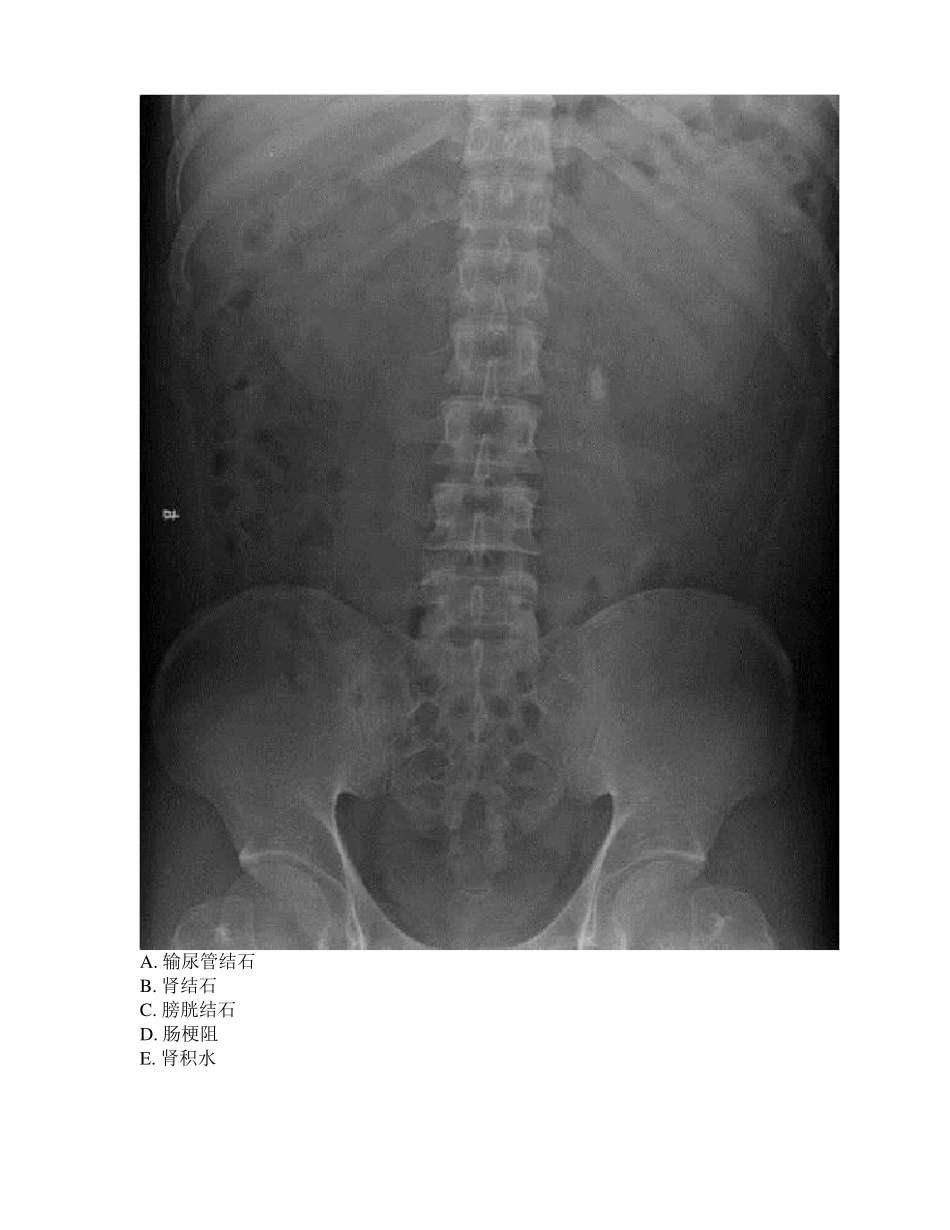

2019 年《临床辅助结果判读》试卷-内科1.【A2 型题】 女性,51 岁,腹部触及肿块,发现肾功能不全半年。考虑诊断为A. 肾囊肿B. 肾脓肿C. 多囊肾D. 肾积水E. 肾盂肾炎2.【A2 型题】 女性,72 岁,突发心悸 2 小时。考虑诊断为A. 阵发性室上速B. 房扑C. 室速D. 房颤E. 窦性心动过速3.【A2 型题】 男性,21 岁,腰部绞痛伴肉眼血尿 3 小时。考虑诊断为A. 输尿管结石B. 肾结石C. 膀胱结石D. 肠梗阻E. 肾积水4.【A2 型题】 一慢性肺心病患者,因呼吸困难伴双下肢浮肿住院,住院后经抗感染,强心,利尿以后双下肢浮肿减轻,但出现恶心,烦躁。血气结果示:pH7.41,PaCO2 9.67kPa(67mmHg),HCO3- 42mmol/L,血 Na+ 140mmol/L,Cl-90 mmol/L。结论为A. 代偿性呼吸性酸中毒B. 代偿性代谢性碱中毒C. 失代偿性呼吸性酸中毒D. 呼酸合并代碱E. 代偿性代谢性酸中毒5.【A2 型题】 男,50 岁,腹胀消瘦食欲减退二月余,有轻度黄染,既往有肝硬化病史,AFP 阳性。诊断为A. 肝硬变B. 肝癌C. 脂肪肝D. 肝脓肿E. 肝炎6.【A2 型题】 患者女性,45 岁咳嗽、发热 20 天,加重伴活动后气促 1 周。诊断为A. 右下肺炎B. 右下肺不张C. 右侧胸腔积液D. 右下肺癌伴肺不张E. 左下肺炎7.【A2 型题】 病史:女,66 岁,反复咳嗽、咳痰 20 年,呼吸困难、伴咯血 2天,诊断A. 肥厚型心肌病B. 风湿性心脏病二尖瓣狭窄C. 风湿性心脏病二尖瓣关闭不全D. 风湿性心脏病主动脉瓣狭窄E. 扩张型心肌病8.【A2 型题】 患者男,65 岁,以“左下腹痛伴便血 2 月”入院。肠镜提示距肛20CM 见一新生物,占据肠腔 1 周,内镜不能通过。诊断为A. 结肠溃疡B. 结肠平滑肌瘤C. 结肠癌D. 结肠息肉E. 慢性结肠炎9.【A2 型题】 患者男性,56 岁,主诉:咳嗽 2 月余。诊断为A. 右上浸润性结核B. 右上肺炎C. 右上周围型肺癌D. 左上肺结核球E. 左上肺炎10.【A2 型题】 患者男,67 岁,以“左上腹痛伴腰背部放射痛半年”入院。患者此次入院 B 超发现有“胰腺团块状回声改变,密度不均”。CA199 6844KU/L,该患者首先考虑的诊断为A. 急性胰腺炎B. 慢性胰腺炎C. 胰腺癌D. 胰腺脓肿E. 胰腺囊肿11.【A2 型题】 患者男性,59 岁,吸烟史 30 余年。乏力,咳嗽 1 月来院。查:血钠 120mmol/L。患者低钠最可能的原因是什么A. 甲亢B. 甲减C. 副癌综合征D. 肺炎E. 肺结核12.【A2 型题】 ...